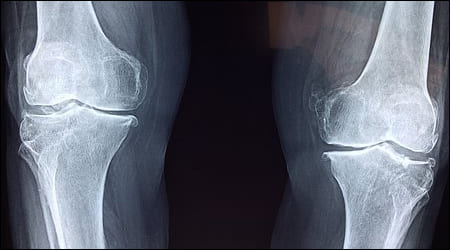

3) 뼈, 근육 약화

뼈와 근육의 약화도 대표적인 비타민 D 부족 증상 중 하나입니다. 마그네슘은 뼈와 근육을 건강하게 유지하는데 꼭 필요한 미네랄 성분인데 불균형한 상태가 되어 몸에 영향을 끼칠 수 있습니다. 또한 칼슘 흡수가 어려워져 골다공증과 골연화증 증상이 생길 수 있다고 합니다.